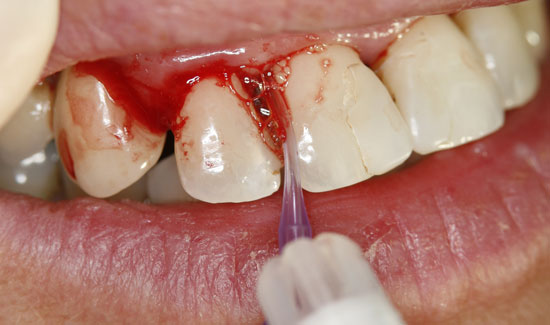

Abb. 2: Klinischer Aspekt der Regio 12, Entstehung von Gasblasen am entzündeten Gewebe. Fortlaufende Absaugung in der Nähe des Einsatzgebietes

Als Ozongasspender verwendeten wir Prozone, das mit Hilfe von Kunststoffansätzen Ozongas schmerzarm in die Taschen einzuleiten erlaubt. Die lokale Ozongas-applikation wurde dreimal im Wochenabstand wiederholt. Außerdem wurde die Patientin auf notwendige persönliche Hygienemaßnahmen aufmerksam gemacht. Wir konnten nicht nur die Blutungen stoppen, sondern den Lockerungs-grad der Zähne in einem stabilen Zustand (2) halten und die messbare Taschentiefe verringern.